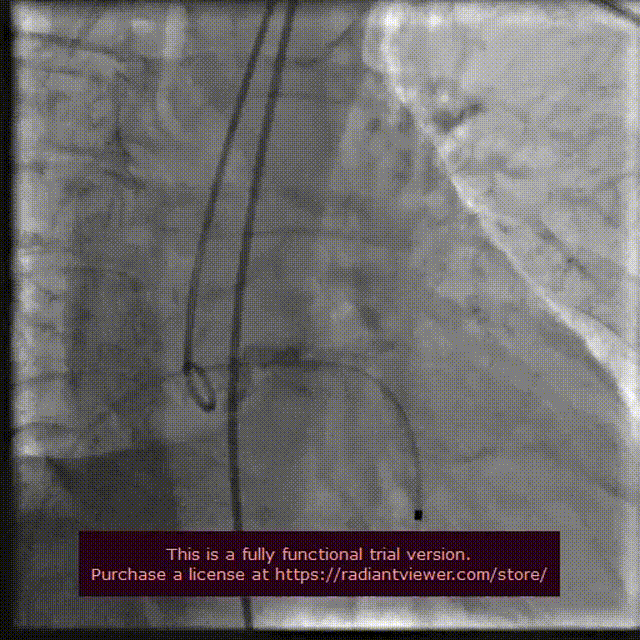

18 mm球囊预扩

输送系统定位

VenusA-Plus®释放过程

18 mm球囊后扩

瓣膜完整形态

术者团队观察到瓣膜形态未能完全伸展,为取得更好治疗效果,后续予以后扩处理。采用18 mm球囊进行后扩后扩,行主动脉造影提示瓣膜置入位置良好、形态完整。